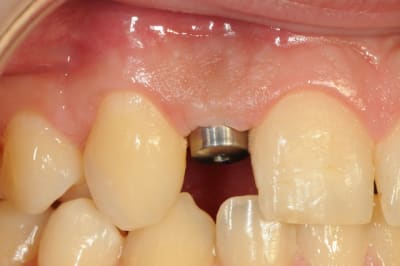

01/09/2010 à 16h54

-1 ou 2 mois plus tard ( je sais plus)

- empreinte avec transfert pop in

- pilier zircone esthétique Axiom

- prothèse et pilier

- pilier zircone en place

- couronne en place (petite compression gingivale)

fin du traitement